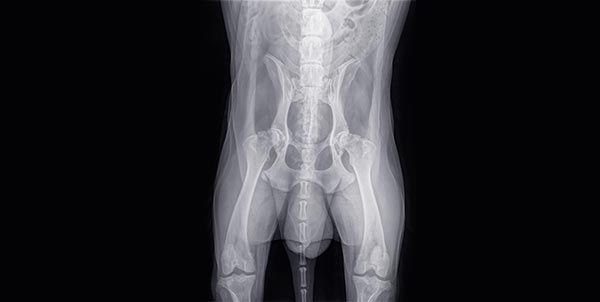

E’ una delle patologie su base genetica di questa razza, le altre sono la clad, depigmentazione del tartufo, prognatismo, atrofia progressiva retinica, ecc...La displasia dell’anca è localizzata a livello del treno posteriore e più precisamente la lesione, quando è presente, è a livello dell’articolazione coxofemorale (articolazione testa del femore con bacino).Possono essere interessate le due articolazioni e allora si definisce displasia bilaterale dell’anca oppure colpire una sola articolazione e la si definisce displasia destra o sinistra.E’ una patologia presente in tantissime razze da caccia, da compagnia e da lavoro.Oggi si tirano in ballo fattori poligenici per spiegare l’origine di tale problema e inoltre vi sono cause alimentari come alimentazione ad libitum, eccesso di calcio e probabilmente anche alcuni criteri di selezione effettuati sulla costruzione dell’arto posteriore del cane.Vi sono alcune linee di sangue o famiglie dove tale problema ricorre con una certa frequenza, clinicamente si hanno problemi di deambulazione con zoppie più o meni accentuate; nelle forme più gravi e bilaterali si può avere l’atrofia completa del treno posteriore con cuccioli di 5 o 6 mesi riluttanti alla deambulazione o con cuccioli che molto spesso assumono la posizione di cane seduto.Nello specifico, tengo a precisare, che tale patologia la si evidenzia con una radiografia effettuata con cane in anestesia generale e proiezione antero posteriore del bacino con allineamento dei due femori.Vi sono alcuni veterinari abilitati ad effettuare tale RX; nella nostra razza, visto il peso medio del cane, tale radiografia la si effettua ad un anno di età.Il cane viene identificato a mezzo microchip; si esegue la radiografia, il veterinario effettua la lettura e successivamente va inviata ad un centro ufficiale di lettura, l’esito della lettura va comunicato a mezzo società specializzata all’ENCI, la quale provvederà a pubblicare sul pedigree del cane il tipo di displasia.I gradi della displasia sono:a) Per una articolazione normaleb) Quasi normalec) Lieve displasiad) Displasiae) GraveLa valutazione dei vari gradi viene fatta con la lettura di un angolo formato dalla intersezione della retta che passa per le due teste dei femori con quella che passa anteriormente al margine superiore dei due acetaboli.Tengo a precisare che l’articolazione toxo femorale comprende oltre alla base ossea della testa del femore anche capsule articolari e legamenti per cui una non perfetta articolazione nel suo insieme che può essere dovuto sia ad una testa piatta, più piccola, sarà causa di artrosi precoci nel soggetto con algie articolari e sintomi più o meno gravi.Come ho accennato precedentemente, quando la displasia è di grado elevato si può avere la sublussazione o la lussazione della testa del femore mentre nelle lesioni di grado inferiore si possono apprezzare solo lievi appiattimenti della testa del femore e artrosi dell’articolazione in questione.Questi sintomi possono comparire attorno ai sei mesi di età del cucciolo e molto spesso al ritorno da caccia di un cane con displasia di non grave entità si può notare l’appoggio in punta dell’arto posteriore.Una volta si diceva che il cane affetto da questa patologia tendeva con difficoltà a salire le scale, aveva un tono muscolare del treno posteriore atrofico e non tenderà mai a saltare sugli arti posteriori.Anche con la selezione di cani in possesso di anca corta si può determinare la predisposizione a tale patologia; infatti i cani che non hanno un appiombo in laterale perpendicolare alla retta passante per l’articolazione toxo femorale ma presentano un metatarso molto all’infuori del quadrato o del rettangolo del cane sono predisposti a tale patologia per cui l’anca dovrebbe essere abbastanza lunga e robusta.Anche l’alimentazione con eccesso di proteine o carboidrati e l’ambiente dove si tiene il cucciolo (pavimenti in cemento oppure su mattoni) possono far insorgere delle micro lesioni articolari e predisporre il cucciolo a tale patologia.Per bypassare tale problema oggi molte società specialistiche impongono la radiografia dei riproduttori.Soprattutto è fondamentale che il cucciolo nasca e cresca con basi sane e sia esposto per molto tempo ai raggi solari, sia privo di parassiti, e teniamo sempre bene in mente che sarà del tutto inutile far correre un cucciolo di 5/6 mesi dietro ad un adulto; piuttosto, sarà più utile farlo maturare e non forzare i tempi di attesa.Questo è indispensabile per avere un eventuale puro sangue sano.